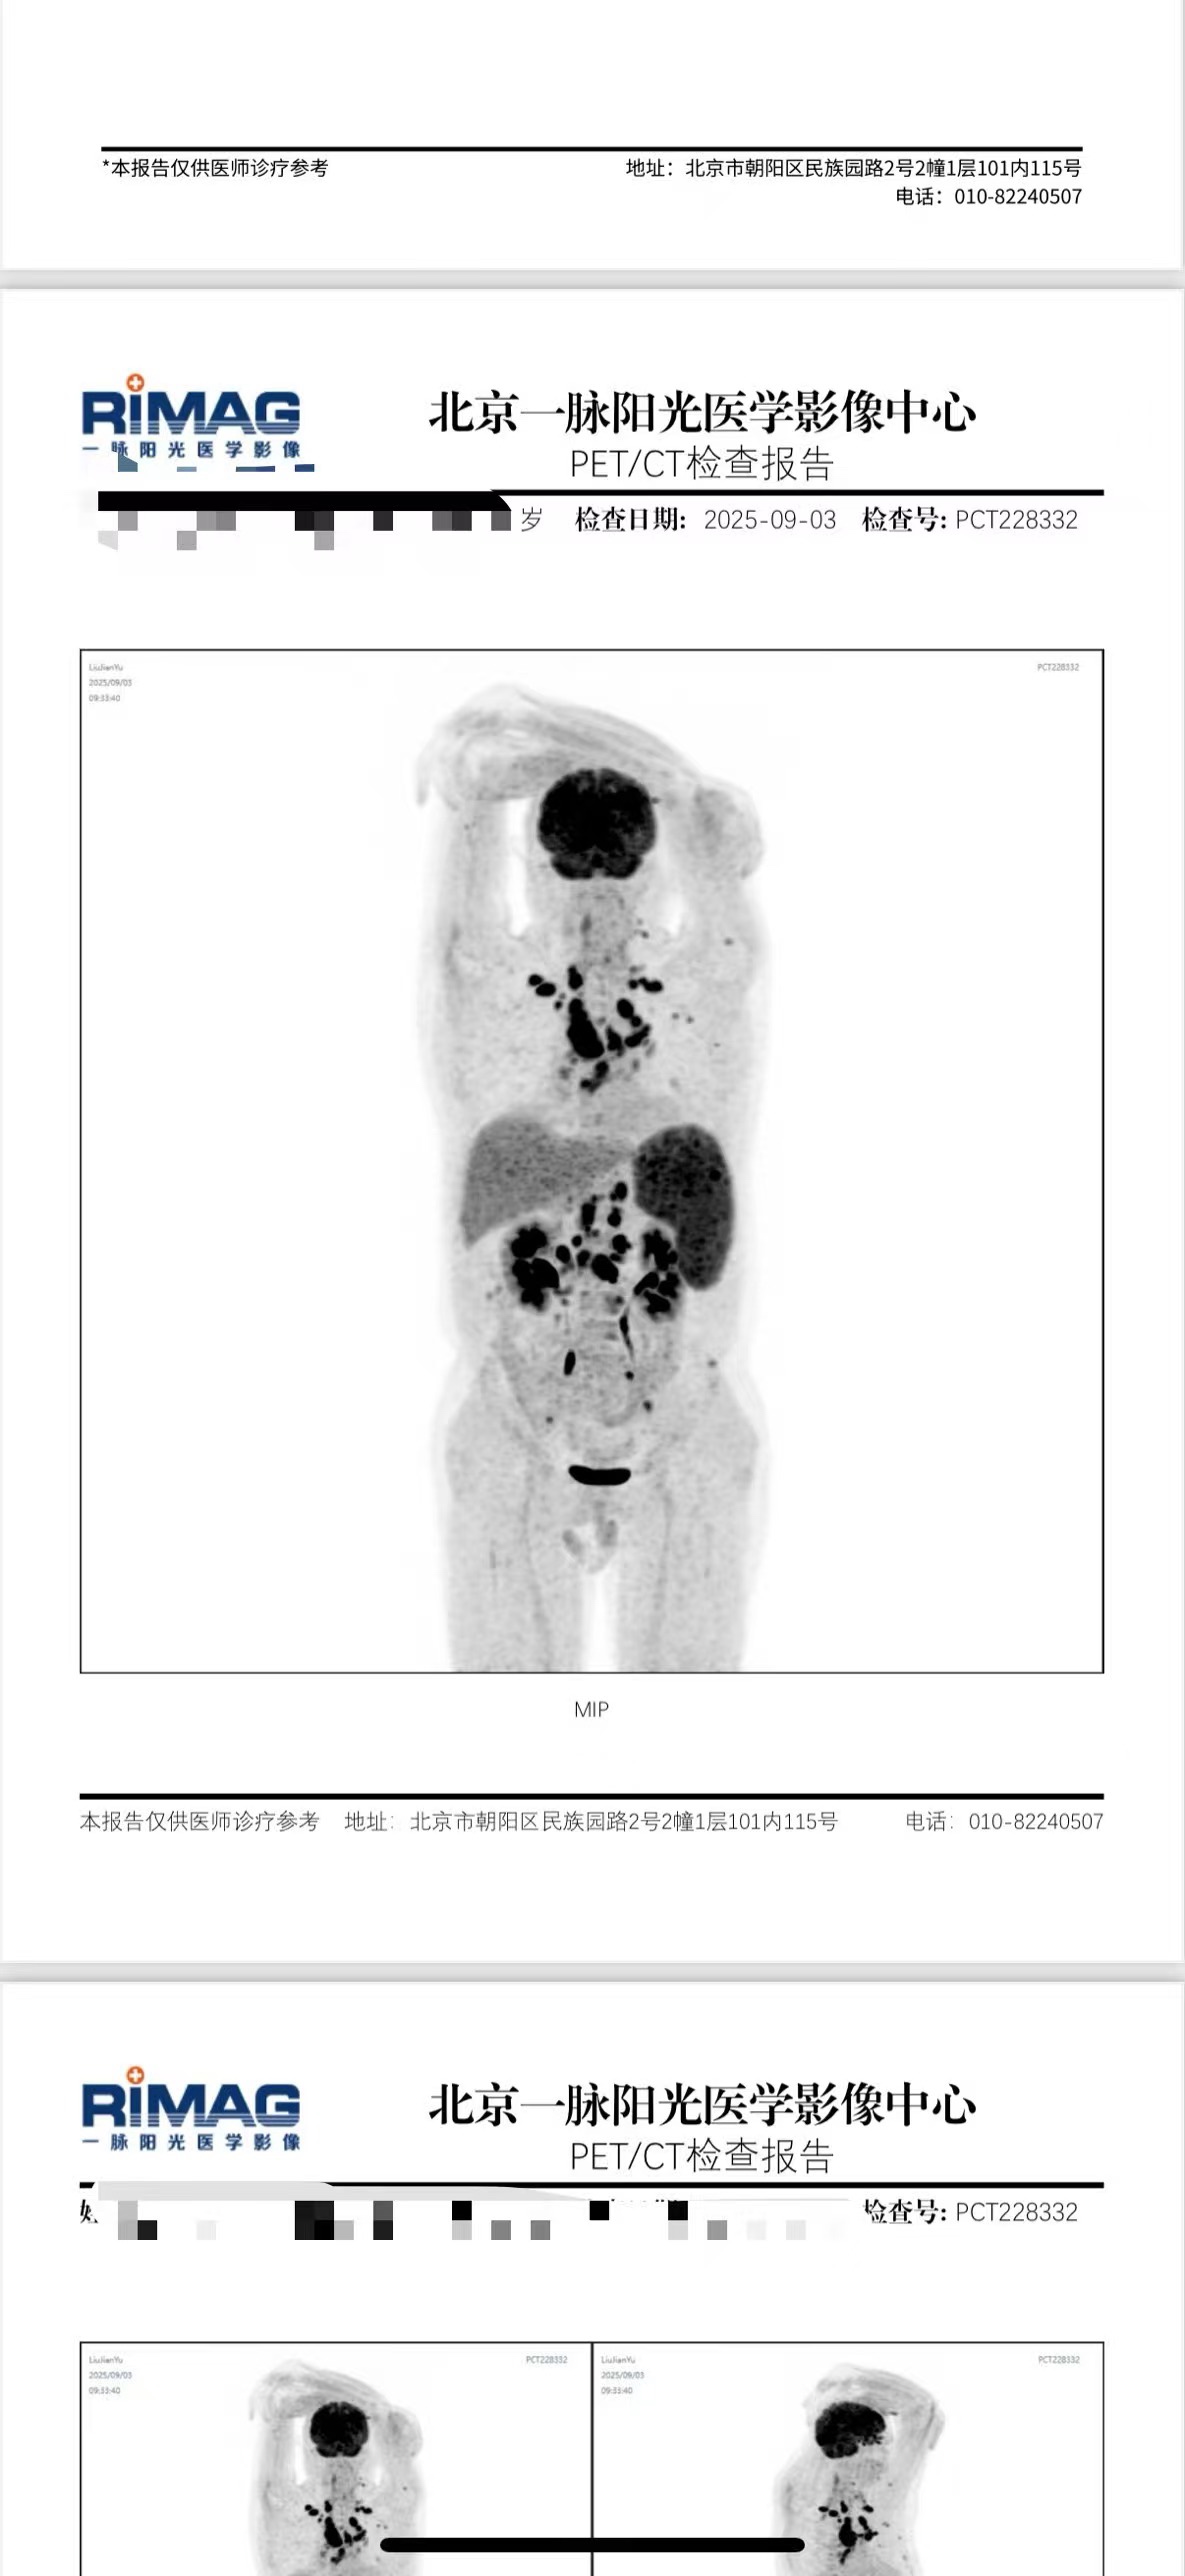

雨丝老师您好,自体复发后,经过大半年的靶向药单抗维持,效果不好,现希望异体移植,在北京陆道培薛主任下。之前本想做cart-t cd7减瘤桥接异体移植。但目前医生说要直接异体,肿瘤负荷不大。

但pet-ct和骨穿都有残留,真的不需要化疗or cart-t桥接吗?我们之前的主治医生说这样有危险,实在担心。麻烦您看看!万分感谢!

从9月3号的PET来看肿瘤负荷不小啊,如果不能用化疗或者其它办法降下去,移植后复发进展的风险仍然会很大。不做CAR-T的原因也许是CD7弱表达吧。

@橙色雨丝 麻烦您看一下,我们是否需要强移,还是再二线化疗一下?现在血小板一直较低,但真的怕强行异体移植太危险。